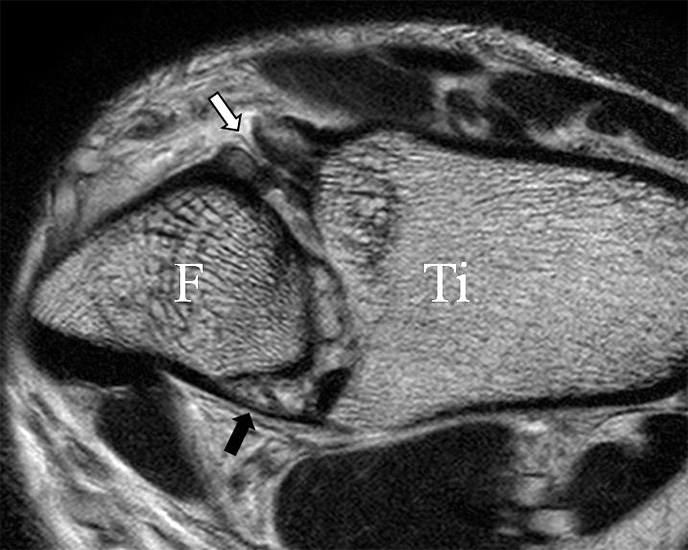

Der Ursprung des Ligamentum fibulocalcaneare liegt unmittelbar kaudal und dorsal des Ursprungs des Ligamentum fibulotalare anterius, so dass gehäuft kombinierte Verletzungen und auch ein gemeinsamer knöcherner Ausriss beobachtet werden. Nach kaudal dorsal verläuft das Band dann nach medial konvex unter die Peroneussehnen. Danach ist ein schräg deszendierender, gestreckter Verlauf bis zum calcanearen Ansatz abgrenzbar (Abb. 10). Dieser zu allen drei Standardebenen schräge Verlauf erschwert häufig die Diagnostik des LFC vor allem bei subtileren Verletzungen. Spezialprojektionen, die dem Bandverlauf orthograd folgen (entweder schräg coronar oder schräg sagittal) erleichtern auch hier die Diagnostik (Abb. 11) insbesondere nicht dislozierter Avulsionen. Assoziierte Verletzungen der Peroneussehnenloge müssen mit beurteilt werden, wobei neben Verletzungen der Sehnen und Sehnenscheiden die Beurteilung des Retinaculum peroneum superius und inferius wichtig ist. In einem Kollektiv von Patienten mit chronischen Außenbandinstabilitäten weisen 50% der Patienten eine Verletzung dieser Strukturen auf 5. Auch hier erleichtern hochauflösende Techniken die Diagnostik (Abb. 12).

Jedoch findet man sich auch hier mit dem Problem der in den Standard-Projektionen schräg verlaufenden Syndesmose konfrontiert. Der oligofaszikuläre Aspekt der vorderen Syndesmose kann in der axialen Schnittebene eine zum Verwechseln ähnliche Morphologie wie eine Ruptur aufweisen (Abb. 15 b und c). Doppelangulierte Schnitte entlang der Achse (schräg koronar/schräg sagittal) lassen hingegen eine eindeutige Beurteilung der Bandstrukturen zu (Abb. 16) und verbessern die Syndesmosendiagnostik.

Bezogen auf die Transversalebene verläuft die Syndesmose ca. 30° schräg cranio-caudal anguliert (Abb. 15 a). Häufig lassen sich drei Hauptfaszikel differenzieren: das kürzeste superiore, das stärkste mittlere und das längste kaudale Faserbündel. Ein akzessorisches Bündel, das anteriore-inferiore, tibiofibulare Ligament (AITFL) oder auch Bassett-Ligament wird in 80-94% der Patienten nachgewiesen 8. Dies weist einen unmittelbaren Bezug zur anterolateralen Talusschulter auf (Abb. 17). In Kombination mit einer Außenbandinstabilität und konsekutivem, talarem Vorschub kann dieses zu einem Impingement an der anterolateralen Taluskante führen mit nachfolgender chondraler oder osteochondraler Läsion.